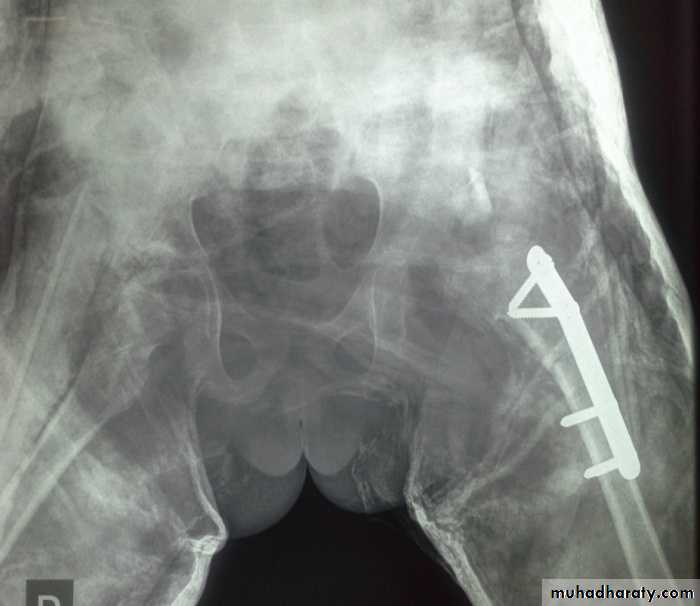

C- if the hip is unredusable from the start or still dislocated after conservative treatment ; then the treatment will be by manipulation under general anesthesia with or without adductor tenotomy with hip P.O.P spica in flexion and abduction for 6 weeks .

D- if close reduction failed, then we should do open reduction